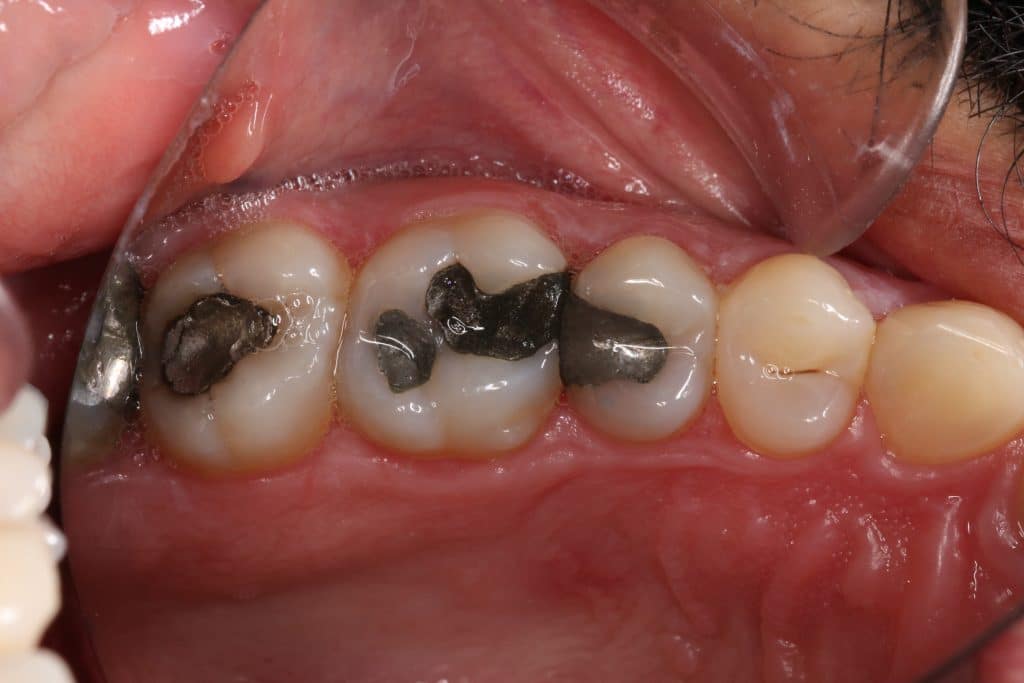

Patient complaining from bad contact and pain during cold 🥶 lasting for few second

decision made to remove old amalgam restoration .